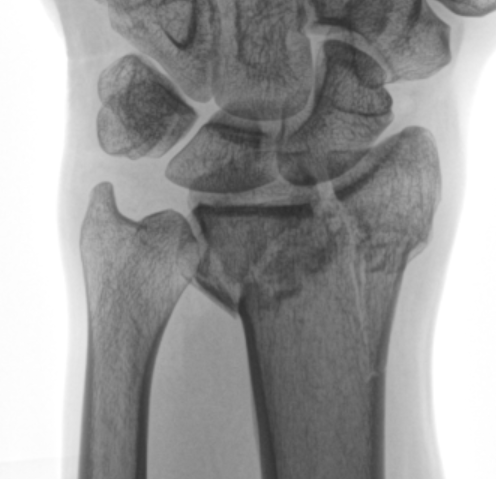

Har du brutit din handled?